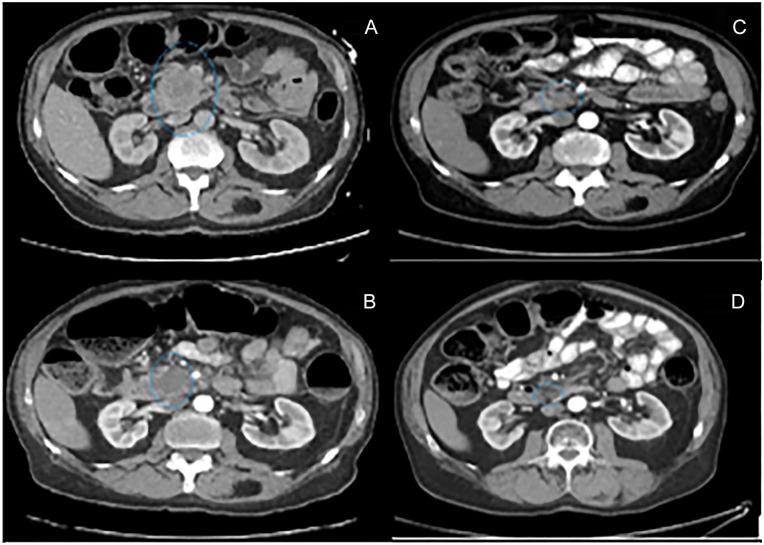

Isolated pancreatic metastases from melanoma are rare with high mortality rate and account for less than 1% of metastatic melanomas. Treatment options are limited with highest overall survival reported in those with complete surgical resection. Of cases reported in the literature with nonsurgical management, highest length of survival was reported to be 10 months. We report a case of malignant melanoma with isolated pancreatic metastasis treated with interferon therapy and immunotherapy, with evidence of progressive tumor shrinkage and survival at 38 months.

孤立性胰腺转移瘤来自黑色素瘤,其死亡率高,占转移性黑色素瘤的比例不到 1%。治疗方案有限,据报道,完全手术切除的患者总生存率最高。在文献中报告的非手术治疗病例中,最长的生存时间为 10 个月。我们报告了一例恶性黑色素瘤伴孤立性胰腺转移,接受干扰素治疗和免疫治疗,肿瘤有进展性缩小的证据,且患者存活 38 个月。